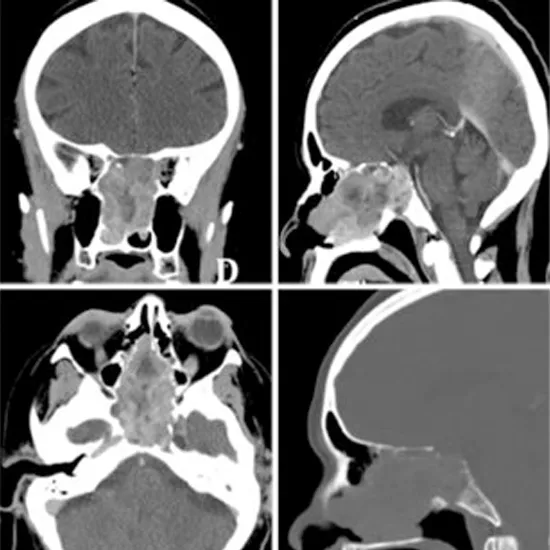

A CECT Sella (Contrast-Enhanced Computed Tomography of the Sell) is an imaging procedure that uses highly focused radiation and contrast media to obtain cross-sectional images of the pituitary sella. Pituitary Sella is a small and bony nook at the base of the skull that protects the brain. It helps in diagnosing and detecting the abnormalities in the sella.